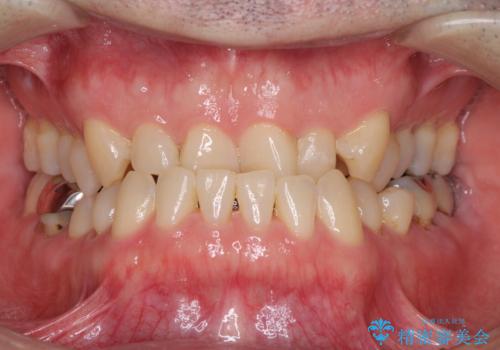

気になる前歯のデコボコと八重歯 ワイヤー矯正ですっきりと

上下ともに歯列幅が狭く、その影響でデコボコになっていたため、ワイヤー装置を用いて歯列を側方に拡大しながら、デコボコを解消していくこととしました。

矯正治療後には気になっていた前歯をセラミッククラウンにし、自然な口元に仕上げることができました。